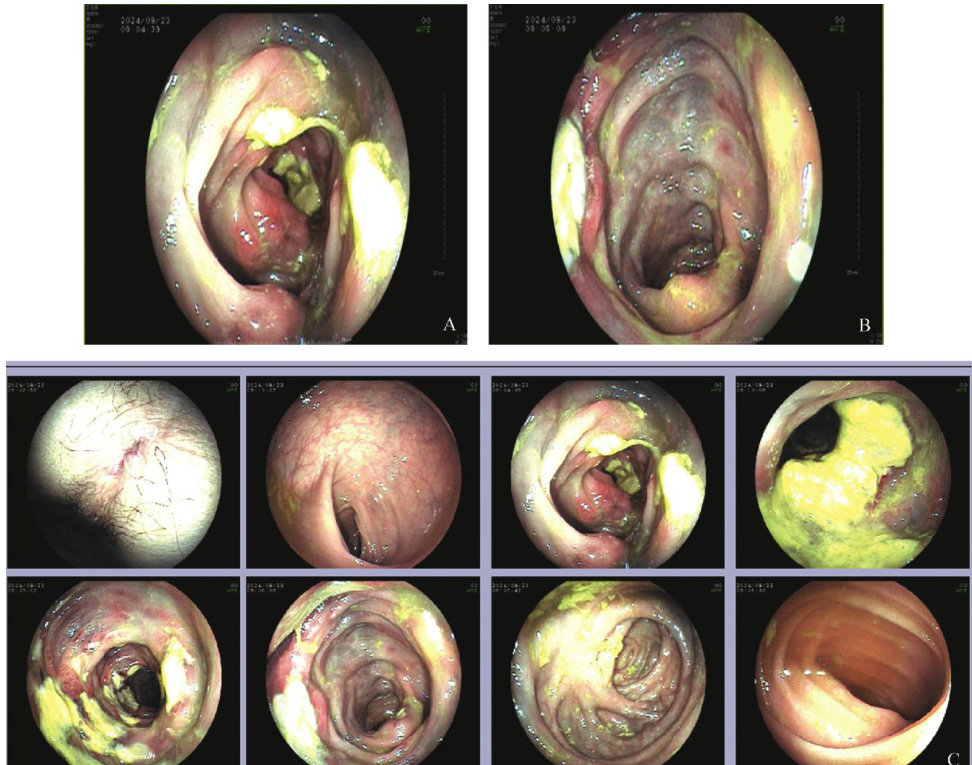

论著·临床研究 | 静脉硬化性结肠炎1例

论著·临床研究 | 静脉硬化性结肠炎1例